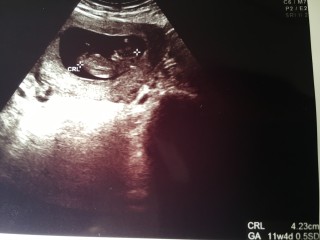

4.5cmと順調に育っててホッとしました。 ただ少し前置胎盤らしく先生からは 「仕事は無理せず適当に」と言われました。 この子の為にものんびり過ごそっかな。